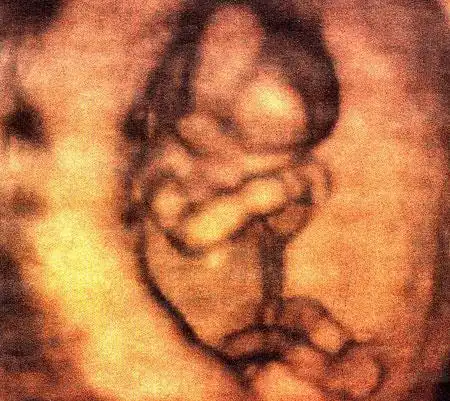

Британские ученые засняли на пленку поведение плода на самых ранних стадиях беременности. Оказывается, зародыш начинает двигаться уже в возрасте 12 недель, вслушивается в голос матери и плачет, когда будущая мама курит...

Уникальная ультразвуковая аппаратура, при помощи которой были получены эти видеозаписи, позволяет не только получать всевозможные фотографии плода, но и наблюдать за ним в реальном времени...

Создатель этой системы профессор Стюарт Кэмпбелл, один из ведущих акушеров Соединенного Королевства, стал знаменитостью в мире медицины благодаря снимкам, на которых зародыш улыбается (раньше считалось, что эта способность появляется лишь после рождения)...

Качество изображений превосходное!...

Специалисты признают, что эти снимки, прежде всего помогающие оценить правильность развития плода, завораживают...

Но главное не это. Главное то, что доктор Кэмпбелл доказал, что "настоящим человеком" эмбрион становится уже в 10-11 недель...

Книга профессора потрясла ученых. В частности, в ней ученый утверждает, что ребенок шевелится уже в 12 недель, задолго до того, как мать начинает ощущать его движения...